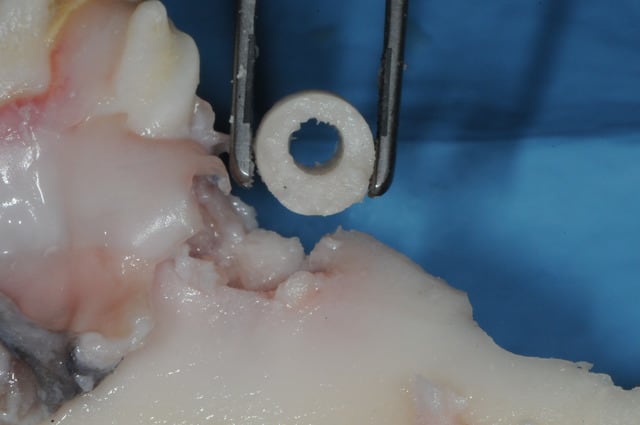

un coup de tréphine in the symphyse.

Palti, Poitras etc... le font assez régulièrement.

La technique s'appelle "bone ring". Technique décrite dans l'article ci joint (merci à Candide Candida qui avait posté ca il y a quelque temps sur nonol) où un implant vient transfixer et stabiliser un bloc osseux.

Dans l'article ci joint il s'agit d'un case report qui manque énormément de support scientifique et cette technique est loin d'avoir fait ces preuves !!

La technique peut sembler alléchante mais est extrêmement osée et très risquée si le but est de placer l'implant en même temps que le bloc osseux.

Giensenhagen sur ces cas aménage le site osseux receveur quand il le peux avec un coup de tréphine identique de celle qui a servi au prélevement.

Il transforme une lacune concave en un puit centré par l'implant dans lequel le greffon vient s'encastrer au moins dans sa partie apicale et plus sur ses parois.

On doit donc avoir une intimité os/os favorable à une intégration du greffon comme dans une technique en onlay classique (sauf que là c'est l'implant qui joue le rôle de fixateur du greffon).

si si olivier, il y a un lit osseux receveur qu'il convient de préparer, sinon, tu as raison, cette technique n'aurait que peu de chance de fonctionner...

on voit mal sur la photo, mais il existe une grosse fraise calibrée qui prépare la partie coronaire de la crête.